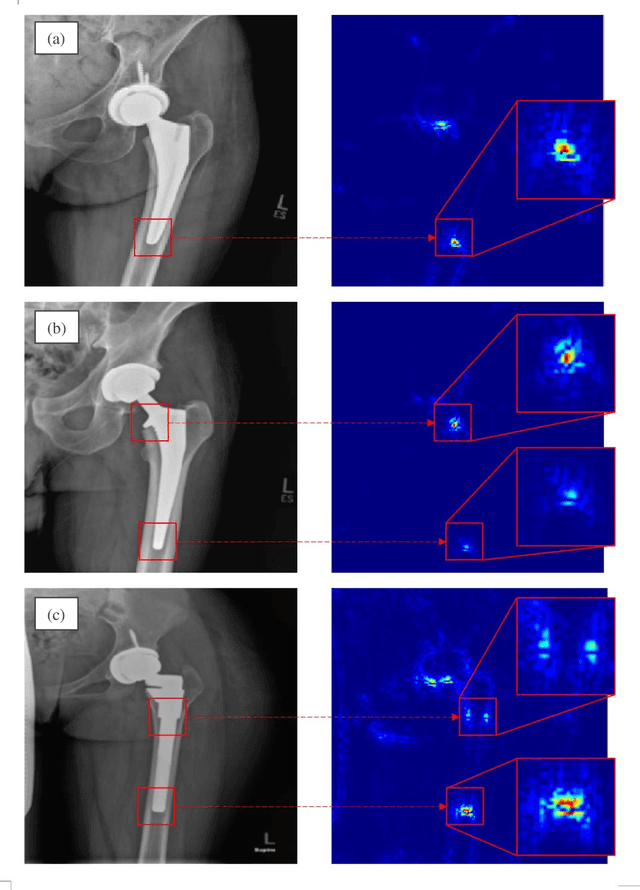

Abstract:Plain radiography is widely used to detect mechanical loosening of total hip replacement (THR) implants. Currently, radiographs are assessed manually by medical professionals, which may be prone to poor inter and intra observer reliability and low accuracy. Furthermore, manual detection of mechanical loosening of THR implants requires experienced clinicians who might not always be readily available, potentially resulting in delayed diagnosis. In this study, we present a novel, fully automatic and interpretable approach to detect mechanical loosening of THR implants from plain radiographs using deep convolutional neural network (CNN). We trained a CNN on 40 patients anteroposterior hip x rays using five fold cross validation and compared its performance with a high volume board certified orthopaedic surgeon (AFC). To increase the confidence in the machine outcome, we also implemented saliency maps to visualize where the CNN looked at to make a diagnosis. CNN outperformed the orthopaedic surgeon in diagnosing mechanical loosening of THR implants achieving significantly higher sensitively (0.94) than the orthopaedic surgeon (0.53) with the same specificity (0.96). The saliency maps showed that the CNN looked at clinically relevant features to make a diagnosis. Such CNNs can be used for automatic radiologic assessment of mechanical loosening of THR implants to supplement the practitioners decision making process, increasing their diagnostic accuracy, and freeing them to engage in more patient centric care.

Abstract:Identifying the design of a failed implant is a key step in preoperative planning of revision total joint arthroplasty. Manual identification of the implant design from radiographic images is time consuming and prone to error. Failure to identify the implant design preoperatively can lead to increased operating room time, more complex surgery, increased blood loss, increased bone loss, increased recovery time, and overall increased healthcare costs. In this study, we present a novel, fully automatic and interpretable approach to identify the design of total hip replacement (THR) implants from plain radiographs using deep convolutional neural network (CNN). CNN achieved 100% accuracy in identification of three commonly used THR implant designs. Such CNN can be used to automatically identify the design of a failed THR implant preoperatively in just a few seconds, saving time and improving the identification accuracy. This can potentially improve patient outcomes, free practitioners time, and reduce healthcare costs.